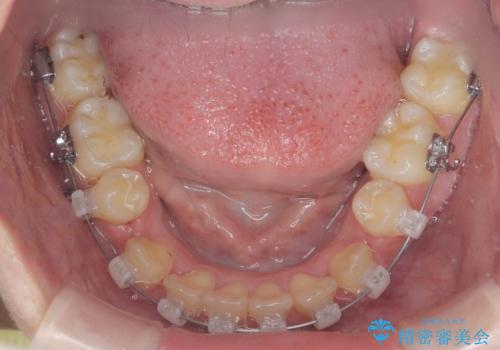

歯並びのせいで歯ブラシがしづらい マルチブラケットを用いた抜歯矯正

- 歯並びのがたつきにより歯ブラシがしづらく、今後虫歯になってしまう不安から、矯正治療を希望されて来院されました。

歯を並べるにはスペースが不足しているため、小臼歯の抜歯を4本行うマルチブラケット矯正による治療を計画します。

治療後は非常に歯ブラシがしやすくなったと、治療結果に満足いただくことができました。